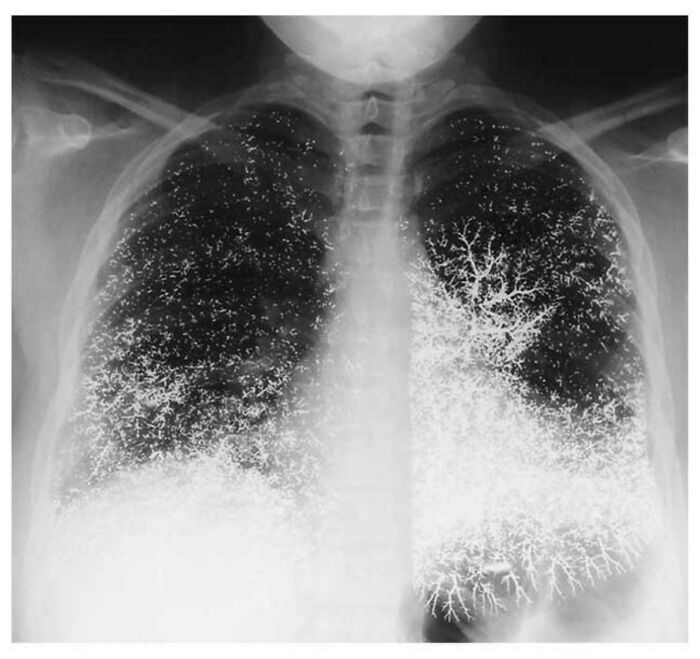

#21 Chest X-Ray Of 21 Yr Old Dental Assistant After Attempting To Take Their Own Life By Intravenously Injecting Elemental Mercury

Image source: EvaGaborsWig